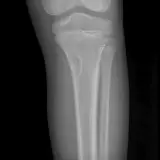

MSK Radiographs